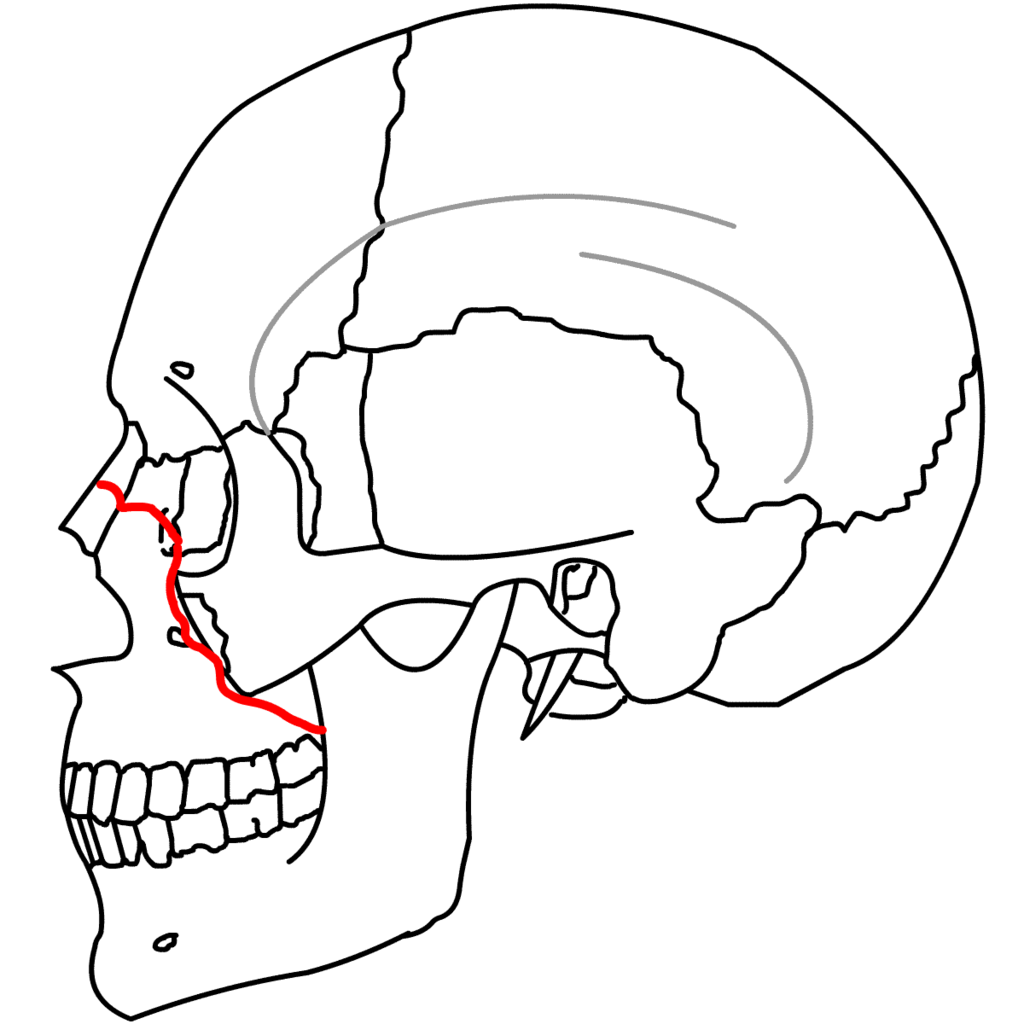

LefortT型骨折

梨状孔下部−犬歯窩−上顎洞壁−翼口蓋裂−翼状突起下部に達する骨折です。

鼻腔底より上方レベルでの水平骨折で、Lefortの3型の中では最も頻度は少ない骨折です。

LefortU型骨折

鼻骨−上顎骨前頭突起−涙骨−篩骨−眼窩底−上顎骨頬骨縫合部−翼口蓋窩−翼状突起に達する骨折です。

LefortV型骨折

鼻骨を横断し、眼窩後壁を経て下眼窩裂、頬骨の前頭突起を通り後方へ向かい、上顎骨と蝶形骨の間を通過する

骨折です。